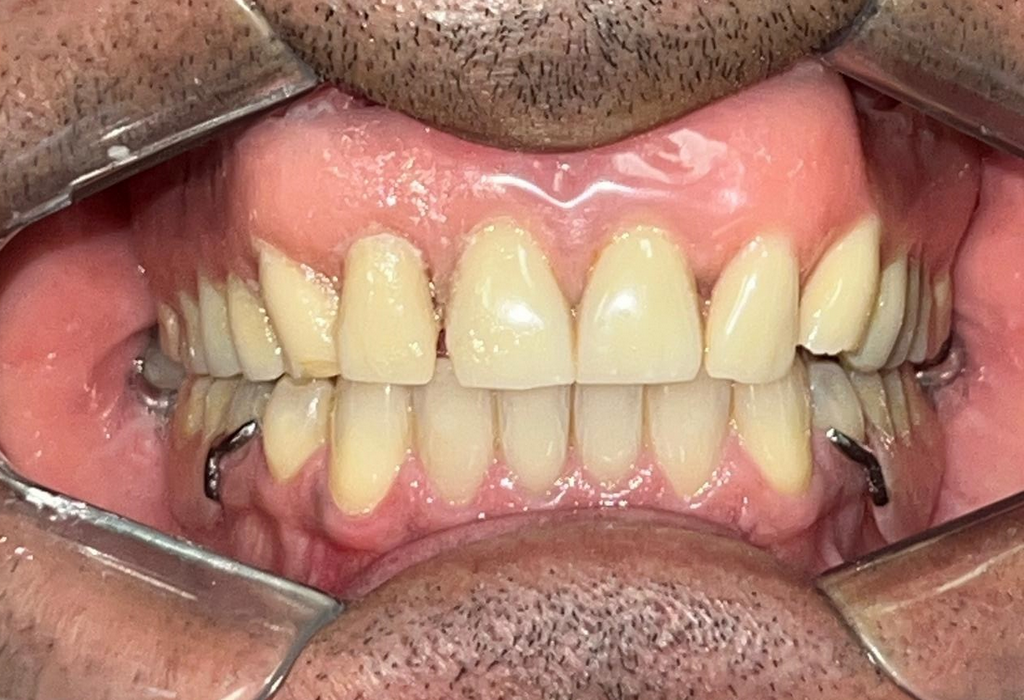

PRÓTESE TOTAL FIXA EM IMPLANTES

C.B.D.S.